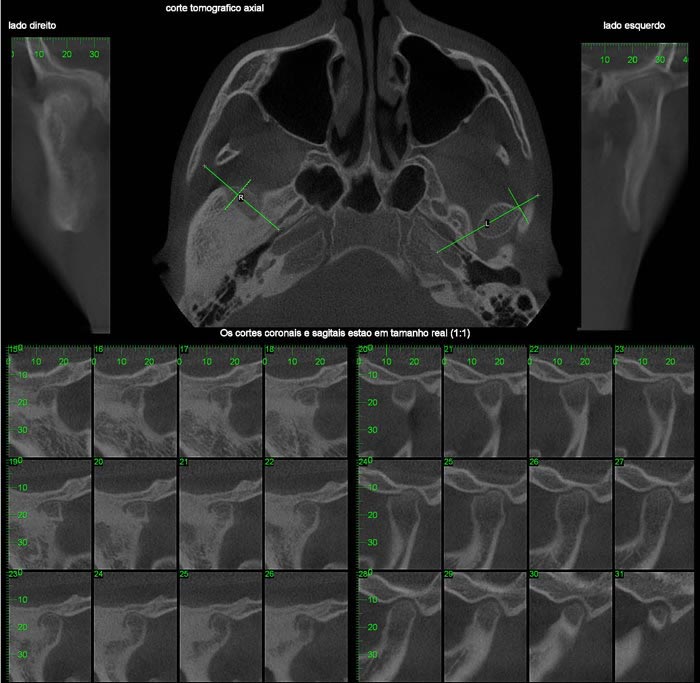

INTERPRETAÇÃO DA TOMOGRAFIA

Na apresentação básica, a reconstrução do exame tomográfico aparece como fatias de imagens

nos três planos: coronal, axial e sagital.

O radiologista “navega” por estas imagens, analisando toda a aquisição e com o auxílio de ferramentas ele monta e escolhe as imagens que irão compor o filme.

Nos softwares há ferramentas que permitem a reconstrução e a obtenção de novos cortes que mostram imagens de uso pontual na odontologia como os cortes transversais e longitudinais.

Os cortes transversais são cortes perpendiculares ao arco da maxila e mandíbula.

Na reconstrução panorâmica aparece uma régua no limite inferior que serve de localização para os cortes transversais.

Os cortes longitudinais são cortes no sentido vestíbulo lingual ou palatino, perpendiculares a uma reta traçada sobre o dente ou a área em questão.

1- A reconstrução panorâmica nada mais é que a representação em forma de panorâmica a partir de um arco criado sobre o rebordo, dessa forma, estruturas fora desses limites de reconstrução não aparecerão, diferente da radiografia panorâmica, onde estruturas “fora do foco” aparecem superpostas e por vezes borradas.

2- Nos cortes sagitais o perfil não muda para lado direito e esquerdo, os cortes são seqüenciais.

3- Por vezes utilizaremos a apresentação das imagens em MIP (Projeção de Intensidade Máxima) que dá o aspecto 3D de crânio seco.